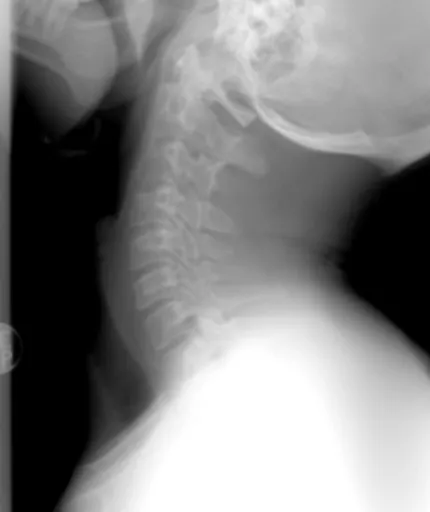

잔기침이 나는 이유 중 가장 흔한 건 아무래도 호흡기 질환 때문일 거예요. 기관지염이나 천식 같은 질병들은 잔기침을 유발하는 대표적인 원인 입니다.

만성 기관지염은 기관지에 염증이 생겨 점액이 과도하게 분비되면서 잔기침을 유발하는 병이에요. 3개월 이상 잔기침이 지속되고, 매년 이런 증상이 2년 이상 반복되면 만성으로 진단 하기도 합니다. 특히 아침에 기침과 함께 가래가 많이 나오는 것이 특징이죠. 흡연이 가장 큰 원인으로 알려져 있어요. 그러니 금연은 필수겠죠?

천식은 기관지가 예민해져서 염증이 생기고 좁아지는 만성 호흡기 질환이에요. 알레르기 반응으로 인해 발생하기도 하는데, 밤이나 새벽에 잔기침이 심해지는 경향 을 보입니다. 숨을 쉴 때 쌕쌕거리는 소리가 나기도 하고, 가슴이 답답하다고 느끼는 분들도 많아요. 잔기침이 나는 이유가 천식이라면 전문의와 꼭 상담이 필요해요.